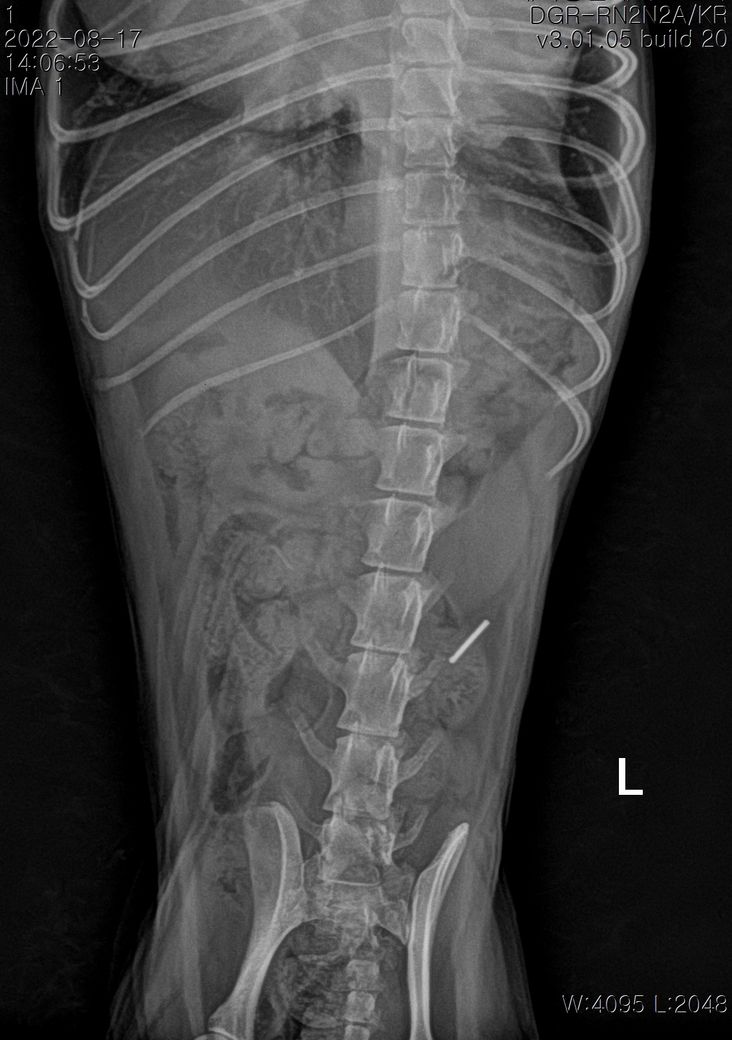

혹시 다른데서 전이가 된것처럼 보이지는 않을까요?

첨부해주신 사진만을 기초로 볼때 폐종양인 경우 좌측 폐전엽부의 종양이, 폐종양이 아닌 경우 종격동내의 종양 특히 흉선종양의 가능성이 높아 보입니다.

물론 폐 종양이 좌측 폐 전엽의 앞쪽 부분에 국한하여 있을 때만을 이야기 하는것으로

만약 좌측 폐전엽의 뒤쪽 부분까지 적출해야 하는 상태의 종양인 경우 수술 이후 호흡 부전이 잘 오고 산소처치를 계속 받으면서 살아야 할 가능성도 고려해야 합니다.

좌측 폐는 산소 교환 능력의 40% 정도를 차지하고 폐엽 절제술 후 산소 교환능에 영향을 주는 기준점이 40% 폐엽이니까요.

현재 위치가 그리 좋지 않은 상태이기 때문에 기대 수명을 말하라면 어렵지만

지금 당장 뇌출혈로 사망해도 이상할게 없는 상태이나 진단과 치료 방향에 따라 훨씬 오랜 기간 생존할 가능성이 있으니 주치의와 잘 상의해 보시는걸 권합니다.